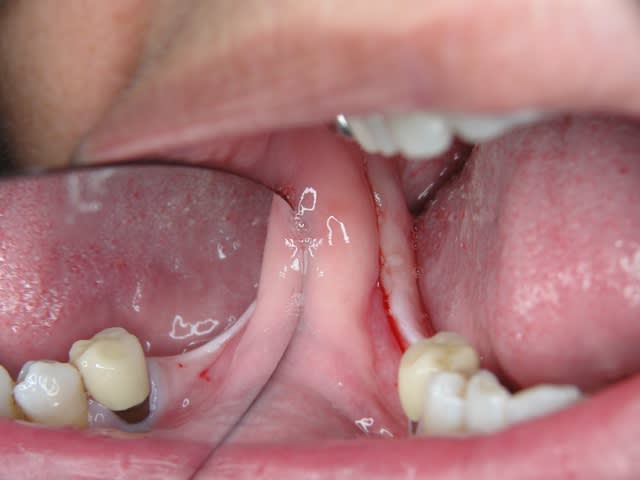

A défaut d'une chir en direct .. voilà une petite histoire en photos ou comment en 90 minutes passer d'un partiel résine à ...7 implants sur provisoires..stabilité primaire 60N grace à la technique MIMI ( oui.. post spécial ce Week end)..:)

Maintenant concernant la demande de scans : je poste ce cas, une patiente vient me voir avec son scan car elle a consulté d'autres "spécialistes" et on lui refuse la pose d'implant secteur 4 où alors avec greffe préalable..Ca se discute..pas de temps à perdre je sais faire autrement..

Avec la chir trans gingivale technique MIMI ( Oui..un post sur la technique bientôt ..) j'ai pu placer deux 3,5/8mm..aurai je eu le meme résultat avec un lambeau..j'en doute..Les couronnes sont en titane. Recul clinique 2 ans ras. Simple efficace rapide moins onéreux satisfaisant pour le praticien et la patiente..